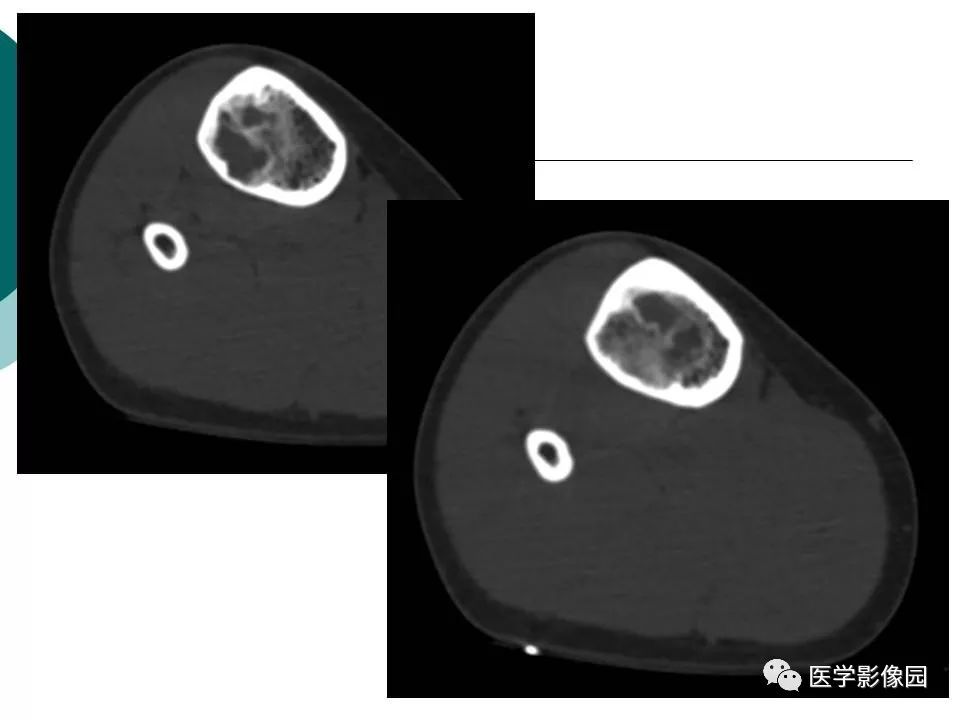

【病例】胫骨非骨化性纤维瘤1例CT及MR